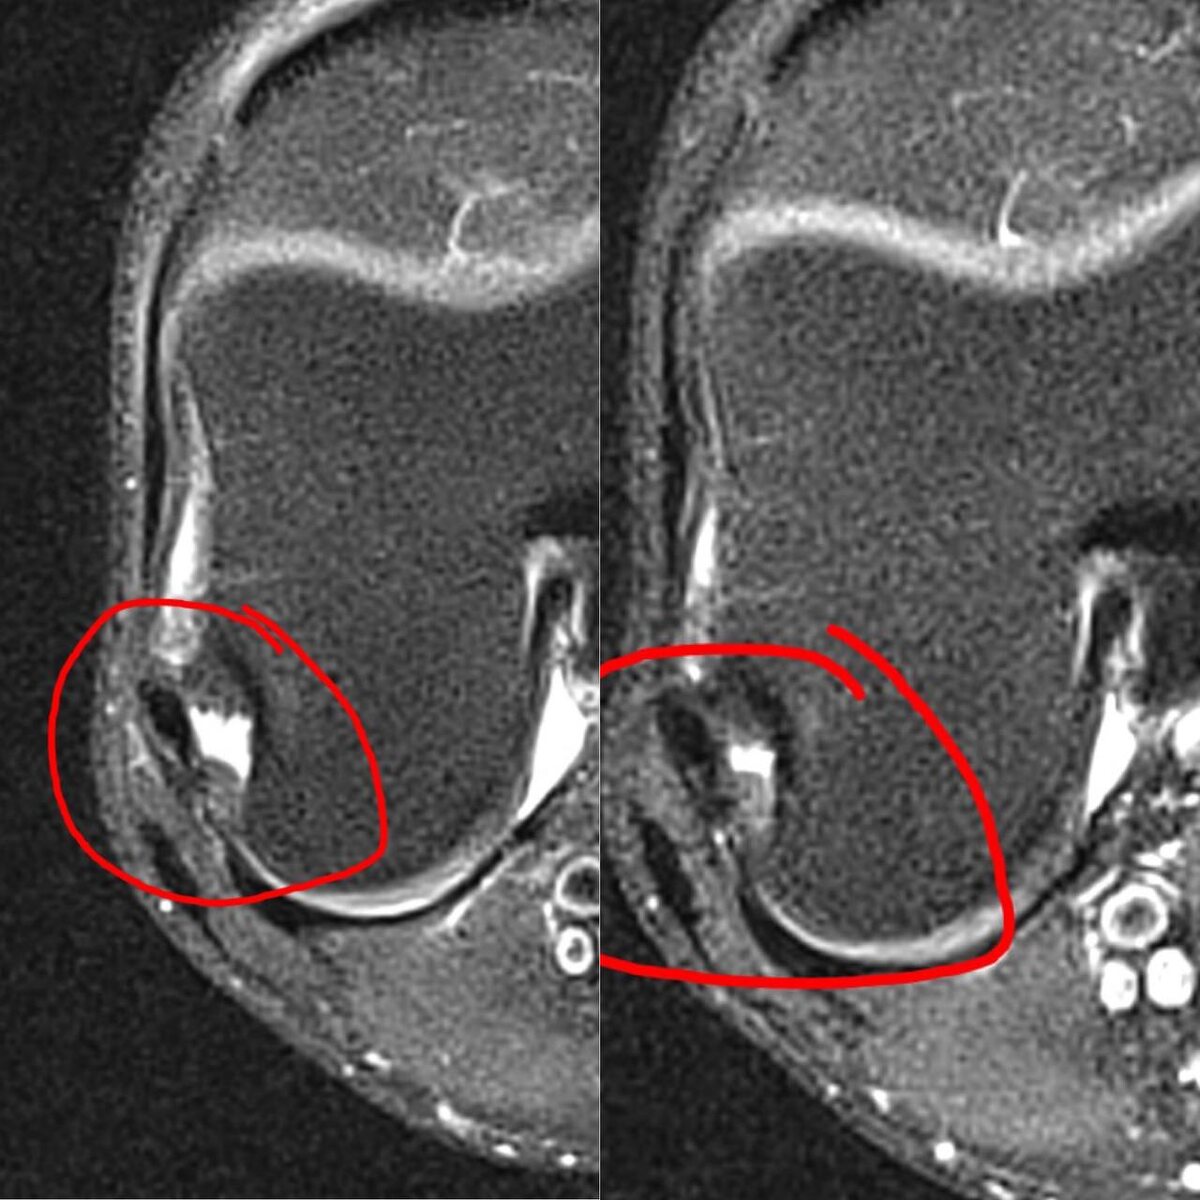

На фото к посту видны изменения по которым чётко видно, что разрыв не закрыт полностью, структура мениска нарушена, но отёчные изменения уменьшились, признаки воспаления ослабли.

Это говорит о стабилизации процесса, но не о полном заживлении.

Динамика указывает на частично заживающий разрыв заднего рога медиального мениска при попытке консервативного лечения.

Если клинически наблюдаются блокировки, боль при нагрузке или ограничение движения — показано артроскопическое вмешательство.